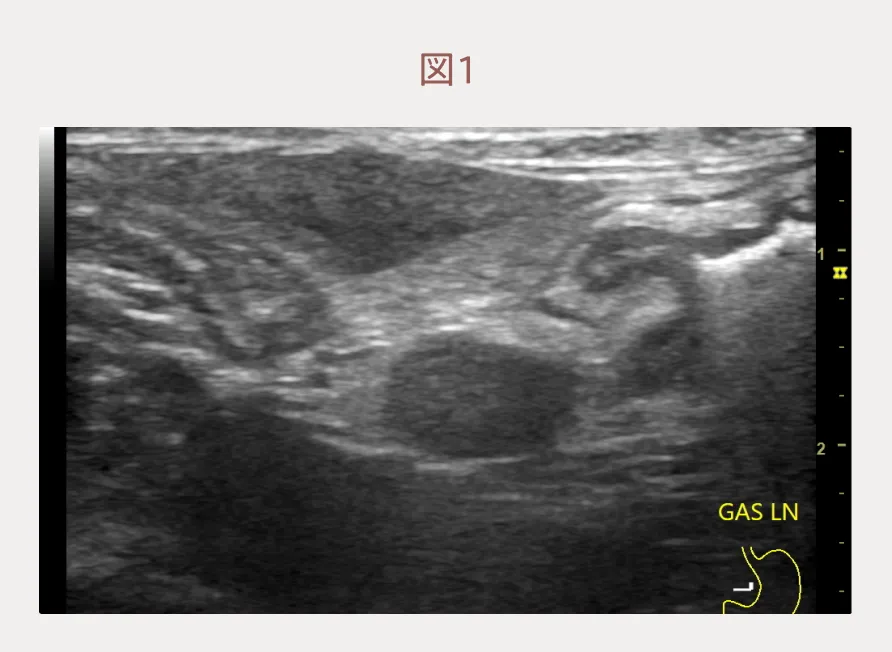

血液検査では特筆すべき異常所見はありません。しかし、エコー検査をすると胃リンパ節は腫大し(図1)、胃壁は一部で壁層構造が不明瞭で(図2)、粘膜面は不整な場所がありました。その他の腸管や内臓に画像的な異常所見はありませんでした。